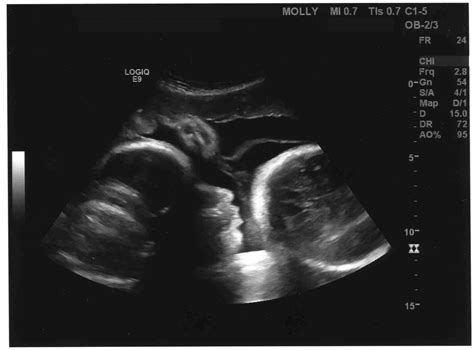

• Assessing Baby's Position: At 36 weeks, the baby should ideally be in a head-down position, ready for birth. If the baby is in a breech or transverse position, the scan can help identify this, and appropriate measures can be taken.

• Baby's Position: The baby is usually in a head-down position, ready for birth. However, some babies may still be in a breech or transverse position.

• What if the baby is not in the optimal position? If the baby is in a breech or transverse position, the healthcare provider will discuss options such as external cephalic version (ECV) or a planned cesarean section.